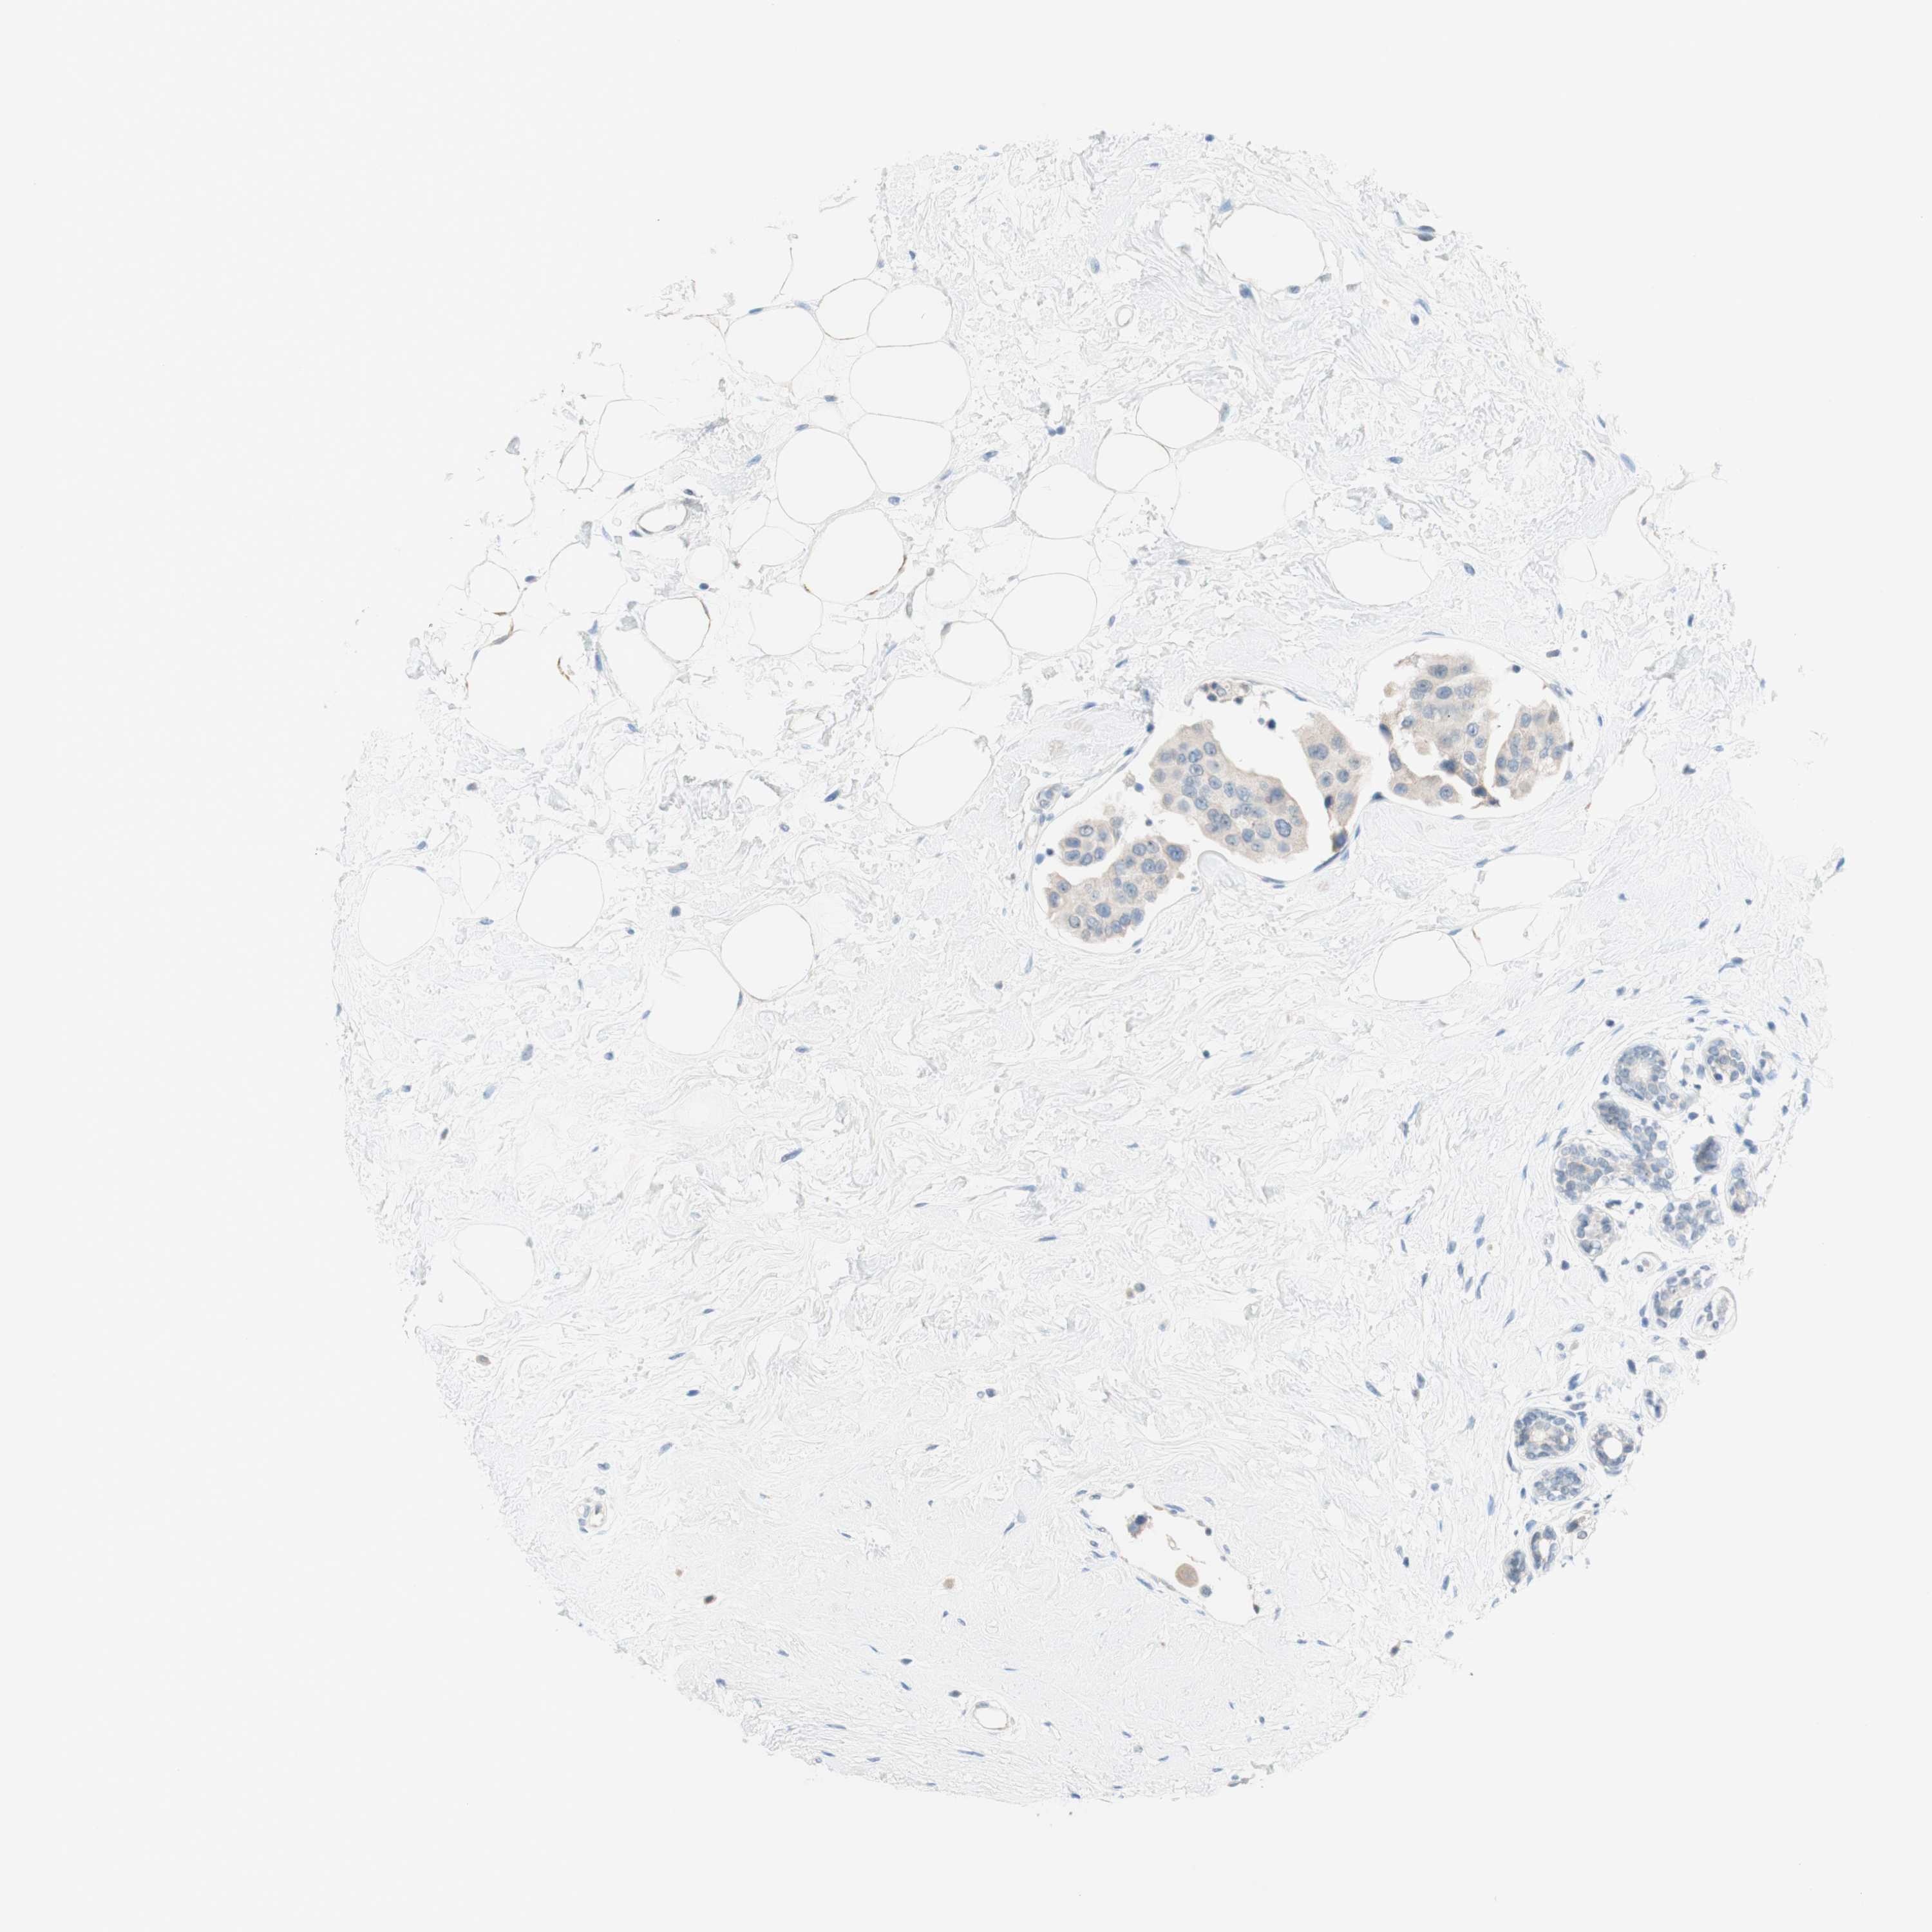

CANCER BREAST CANCER Show tissue menu

BRCA TCGA BRCA VALIDATION PROTEIN EXPRESSION

ANTIBODIES